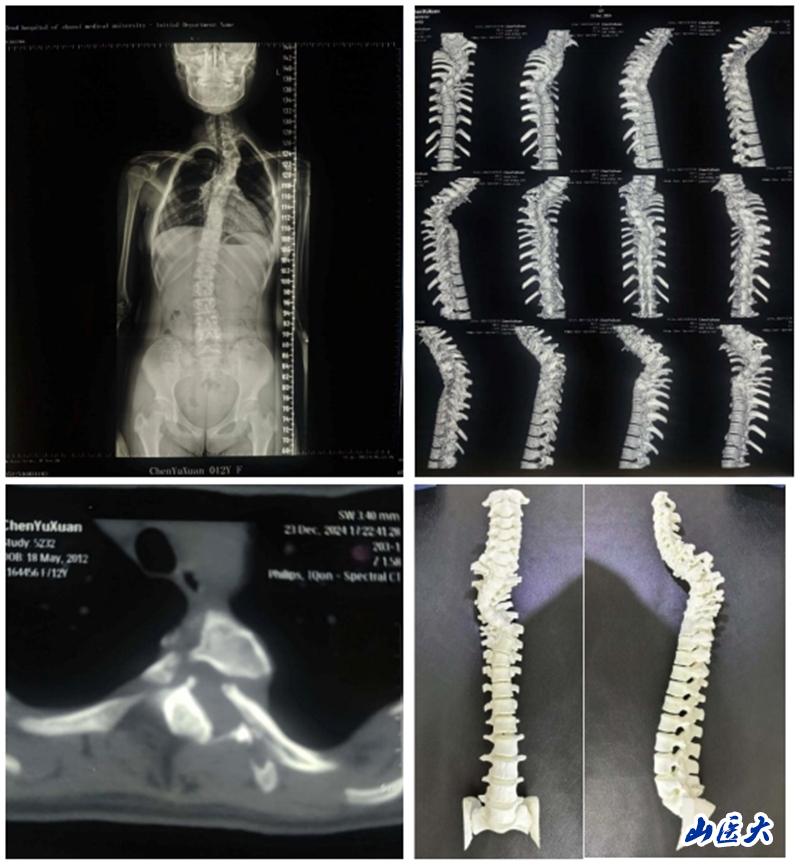

近日,我校第二医院骨科脊柱畸形专业组成功为一名12岁少女解除了因神经纤维瘤病导致的脊柱侧弯之苦。

这位小姑娘自幼便全身布满咖啡斑,但因家庭贫困且对疾病认知不足,一直未进行详细检查。2024年7月,其祖母偶然发现孩子脊柱出现明显畸形,遂展开多方求医之路。在得知我校第二医院骨科脊柱畸形专业组薛旭红教授在脊柱侧弯治疗领域造诣颇深后,患者家属慕名而来,前往我校第二医院骨科门诊就诊。薛旭红凭借深厚的医学理论知识和丰富的临床经验,迅速诊断出患者为神经纤维瘤病所致的脊柱侧弯,并立即安排其住院治疗。进一步检查发现,患者因神经纤维瘤病导致椎体骨破坏严重,椎弓根细小,肋骨头变尖并凸入椎管内,手术难度和风险均极高。

面对如此复杂病情,薛旭红教授与赵胜教授带领团队精心策划,为患者量身定制了个性化的手术方案。2024年12月27日,在主治医师董政权、麻醉医师、器械护士王淑珍和巡回护士杜娟的通力协作下,骨科团队成功完成了这场高难度、高风险的手术。